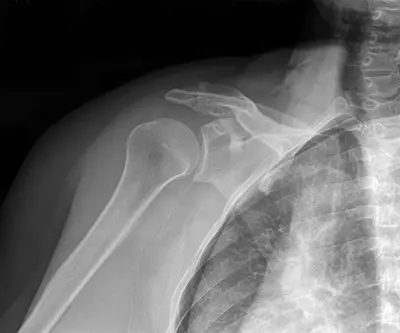

The shoulder joint (glenohumeral joint) is a ball and socket joint where the head of the upper arm bone (humerus) attaches to the shoulder socket (glenoid cavity). Because the socket is shallow, the joint relies on additional structures for stability. The labrum, a ring of cartilage surrounding the socket, deepens the cavity and forms a cup for the humeral head to move within. This structure provides stability while allowing the shoulder’s wide range of motion.

Diagnosis begins with a detailed medical history and physical examination of the shoulder. Imaging tests such as an X-ray or MRI may be ordered to assess the extent of the damage and confirm the presence of a Bankart tear.